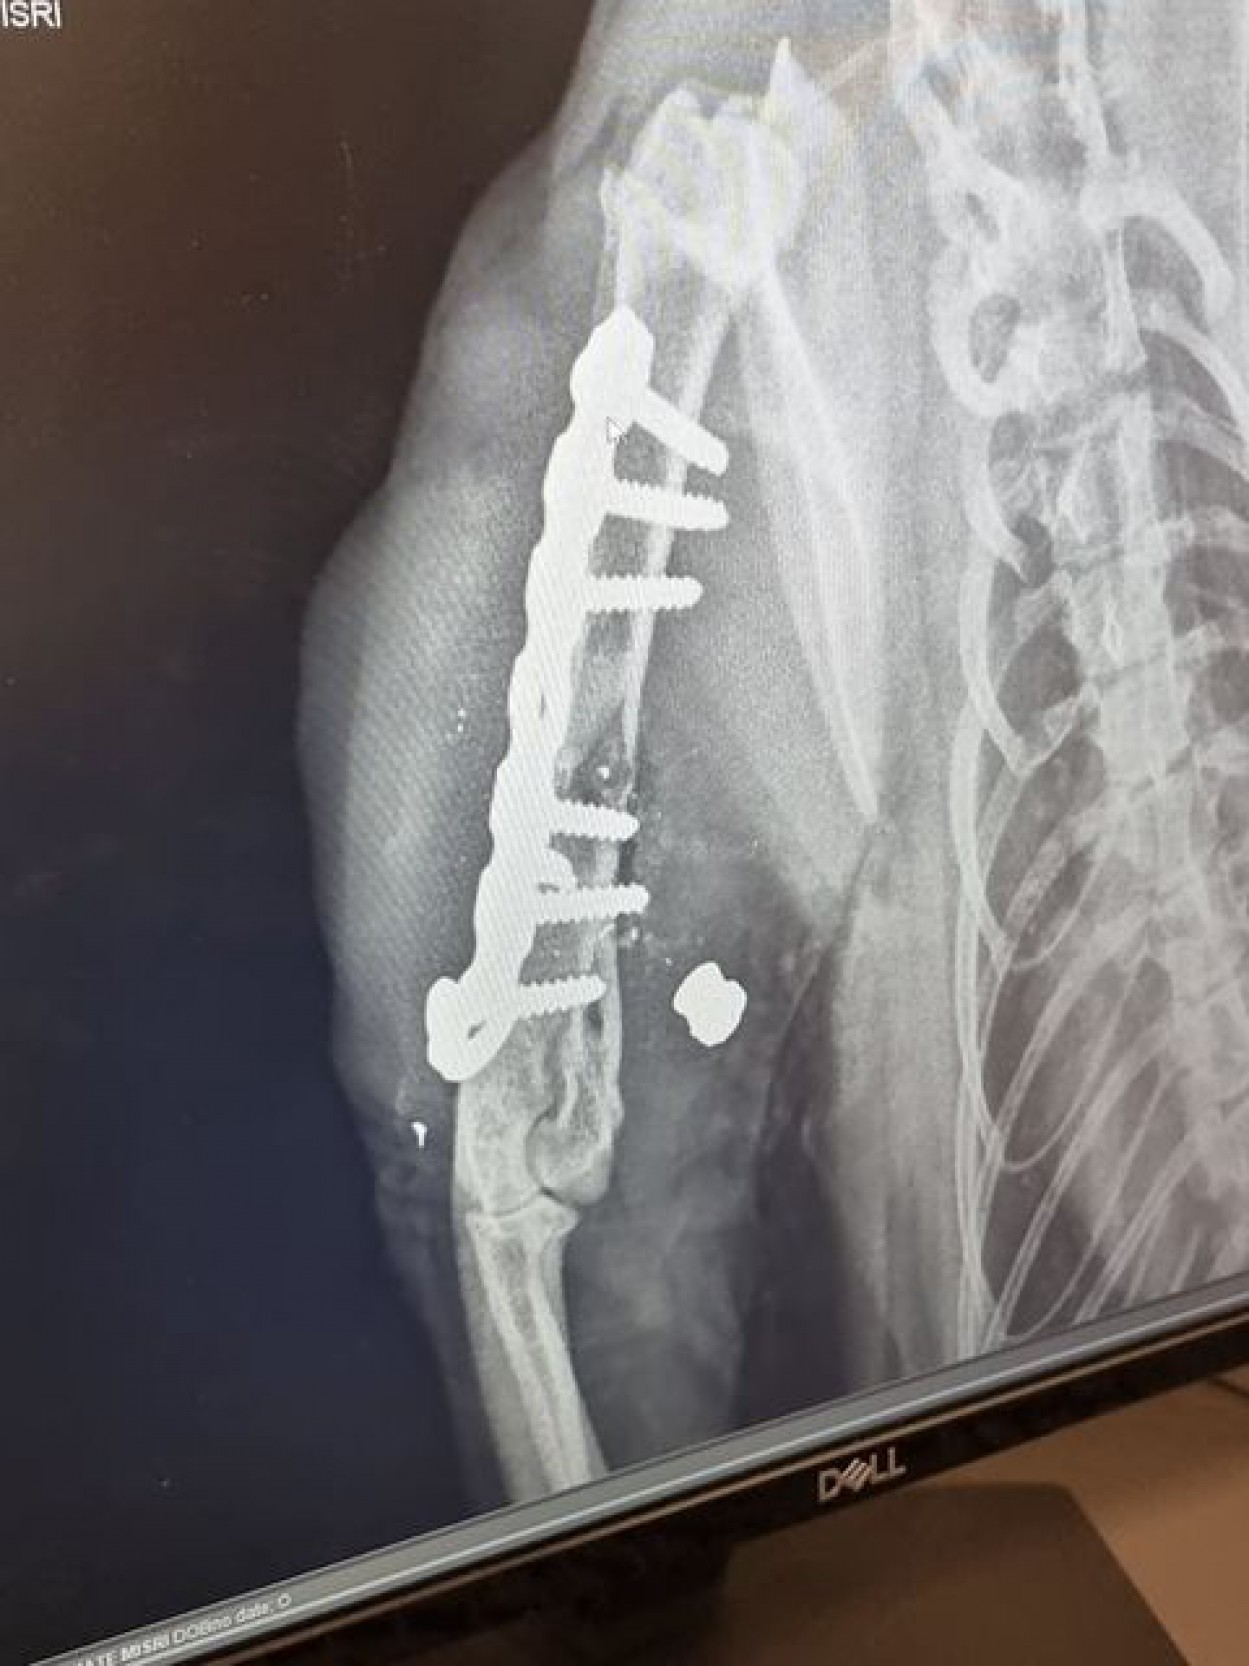

Nuvežėme katę į Jonavoje esančią veterinarijos kliniką. Atlikus rentgenogramą, išgirdome diagnozę: lūžis dėl šūvio", - istoriją nupasakojo moteris.

Šiuo metu katė jau sveiksta po operacijos, kuri truko 2,5val. Į jos koją įdėta plokštelė ir 6 varžtai. Šiai dienai gydymas kainavo 400€. Tai ,žinoma, tikrai dar nėra gydymo pabaiga", - teigė moteris.